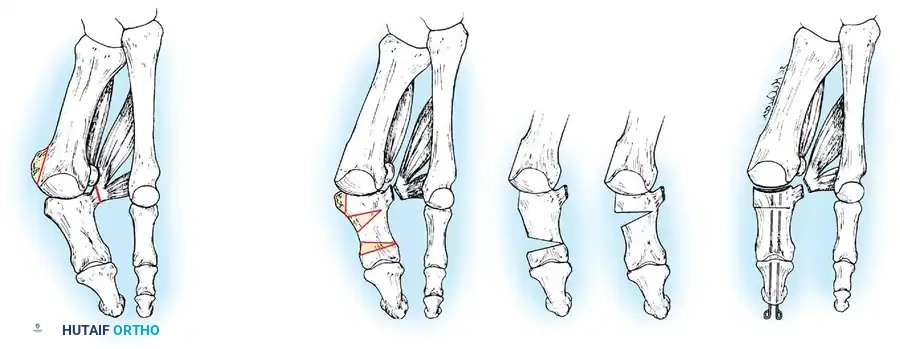

Keller Resection Arthroplasty The Keller procedure combines resection hemiarthroplasty of the fi rst metatarsophalangeal joint with removal of the medial eminence of the fi rst metatarsal (Fig. 78-28). Although removing the base of the proximal phalanx decompresses the joint and mobilizes the hallux, allowing marked correction of valgus, the varus of the fi rst metatarsal is not corrected, and maintaining correction of the valgus of the hallux is diffi cult. Other complications of the Keller procedure have been emphasized in the literature to such an extent (with neither the incidence nor the severity of such complications clearly documented) that the indications for this procedure have been limited severely. In our experience, however, complications are uncommon if patients are selected carefully. Modifi cations in the original technique also have allowed expansion of the indications for the Keller bunionectomy. Candidates for the Keller procedure are patients older than 50 years with moderate-to-severe hallux valgus (30 to 45 degrees); intermetatarsal angles of 13 degrees or less, indicating mild-to-moderate metatarsus primus varus; and pain over the medial eminence with any shoe worn, so the variety of shoes the patient can wear is severely limited. An incongruous fi rst metatarsophalangeal joint caused by

Fig. 78-26 Modifi ed McBride bunionectomy (DuVries; Mann). A, Medial capsule of second metatarsophalangeal joint is sutured to lateral capsule of fi rst metatarsophalangeal joint with interposition of released adductor hallucis. B, Medial capsular resection. C, Confi guration after capsular resection. D, After capsular imbrication, hallux should rest in neutral position or not exceed 5 degrees of varus. E, Postoperative dressing technique (Mann). ( E after Beverly Kessler; courtesy of LTI Medica and The Upjohn Company.) lateral subluxation of the phalanx on the metatarsal head, severe lateral displacement of the sesamoids, and any evidence of degenerative cartilage changes in the joint all are radiographic indications for the Keller procedure. Two modifi cations in technique can expand these indications, however, to include patients with more severe deformities (Fig. 78-29) (but not to include younger patients): fi bular sesamoidectomy and lateral displacement of the fi rst metatarsal. Using these modifi cations, Donley et al. obtained an average 18-degree correction of the metatarsophalangeal angle and an average 6-degree correction of the intermetatarsal angle in 38 patients (50 feet);

95% of patients were satisfi ed with their results. Patients with 50 degrees or more of valgus of the hallux (18 to 20 degrees of varus of the fi rst metatarsal), complete lateral dislocation of the sesamoids, marked degenerative changes, and severe pronation of the hallux may benefi t functionally and cosmetically from alterations of the standard technique.

Fig. 78-29 Severe hallux valgus with bursa formation in 70-year-old woman. A and B, Anteroposterior and lateral clinical photographs of patient’s right foot. C, Correction of deformity by modifi ed Keller procedure. D, Preoperative and postoperative weight bearing radiographs of same patient.